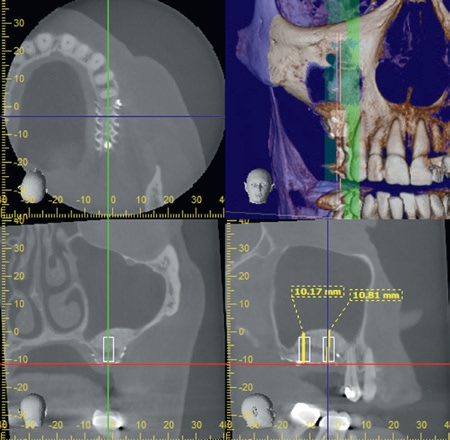

Nach einer Abheilzeit von 10 Wochen wurde im Rahmen der präimplantologischen Diagnostik aufgrund der Komplexität der Defektsituation im 1. Quadranten regio 16 und 17 neben der klinischen Untersuchung eine DVT-Aufnahme angefertigt. Es zeigte sich ein transversaler und vertikaler Knochendefekt mit einer Restknochenhöhe von teilweise nur 1 mm. Zu beachten war auch die Höhe des Knochenlagers, das sich teilweise auf Höhe des Apex des Nachbarzahnes 15 befand (Abb. 1a und b). Dieser dreidimensionale Defekt sollte durch einen externen Sinuslift nach kranial sowie eine ventrale horizontale auflagernde Augmentation ausgeglichen werden. Hierfür wurde mit dem DICOM-Datensatz der DVT-Aufnahme ein virtuelles Modell hergestellt, welches die Planungsgrundlage für das Augmentationsvolumen darstellte (Abb. 1c). Anhand dieser Daten und in Abstimmung mit dem Behandler stellte die ReOss GmbH ein patientenindividuell gedrucktes Titangitter für die Augmentation her.